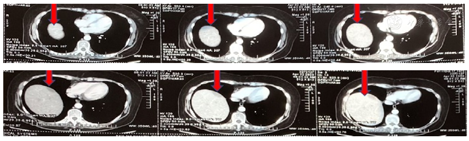

肝转移术后复查增强核磁(2018年11月23日北医三院),见图3。